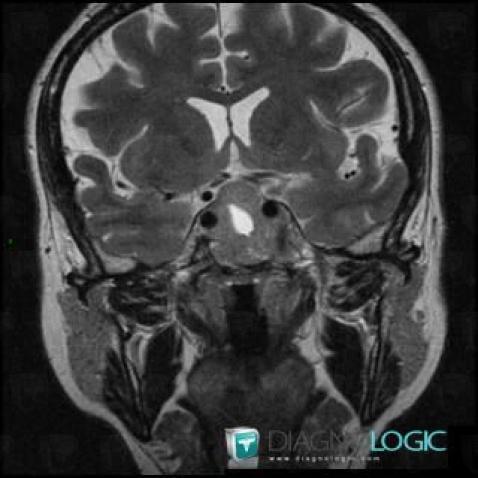

Macroadénome hypophysaire, Hypophyse et région parasellaire, IRM

Voici les informations spécifiques à l'image clé ci dessus:

- Diagnostic Macroadénome hypophysaire, Localisation(s) Hypophyse et région parasellaire, comportant les gammes Lésion du sinus caverneux